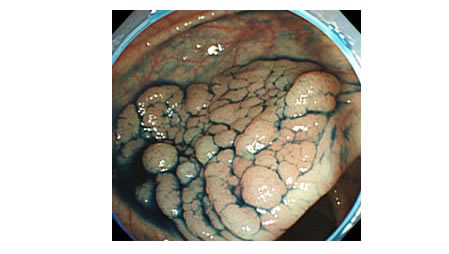

2.色素拡大内視鏡検査

約100倍のズーム機構を搭載した内視鏡を用い、腫瘍の表面構造を詳細に観察します。拡大観察により、良性、悪性、早期癌の進行度などの診断が、一般観察より正確に行うことが可能となり、内視鏡的治療の適応か、手術が必要かの診断が的確に行われます。一般に、インジゴカルミンやクリスタルバイオレットなどの薬液を用い観察を行います。